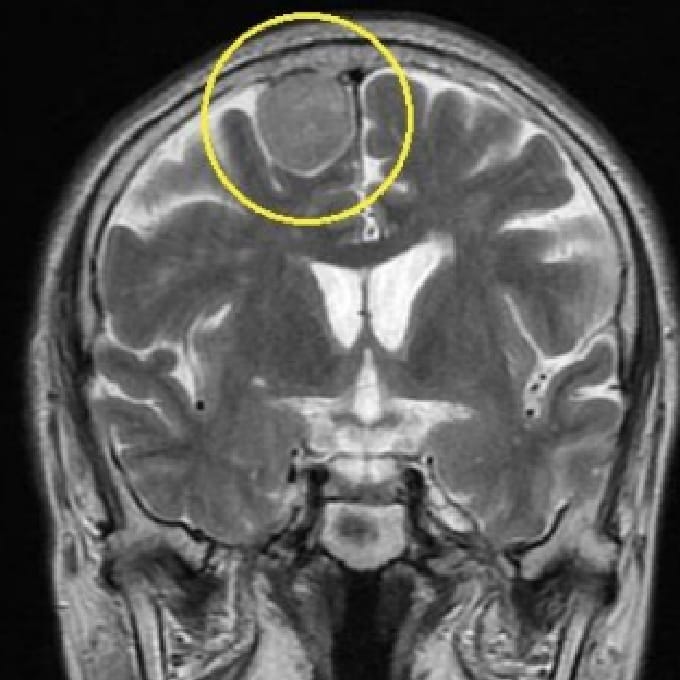

脳腫瘍

下垂体腫瘍

MRIは、脳の断面画像を撮影し、脳そのものの状態を確認する検査です。X線を使用せず、脳梗塞の痕跡(無症候性を含む)や出血の跡、腫瘍などの異常がないかを調べます。MRAはMRIの撮影法の一つで、脳や頸部の血管を画像として写し出し、血管の形や流れの状態を確認する検査です。未破裂脳動脈瘤の疑い、血管の狭窄・閉塞など、脳卒中リスクにつながる所見の確認に役立ちます。